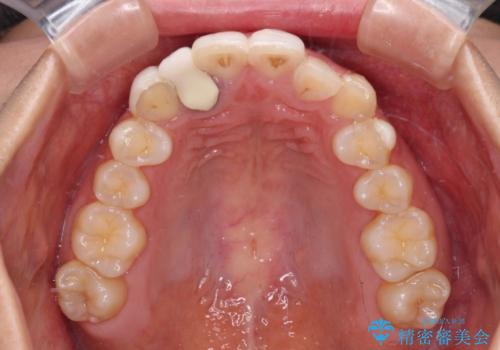

- 上下前歯のデコボコを気にして来院された患者様です。

インビザラインによる上下歯列の拡大と、IPR(歯と歯の間を削る)にるスペースの獲得により、前歯のデコボコを改善することとしました。